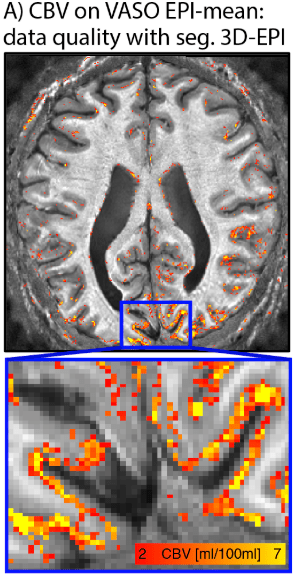

- Ruediger Strinberg and Tony Stoecker implemented a VASO sequence with segmented 3D-EPI readout for SIEMENS VE systems.

Data of this figure were acquired with Stirnberg’s sequence at the 7T Terra at NIH.